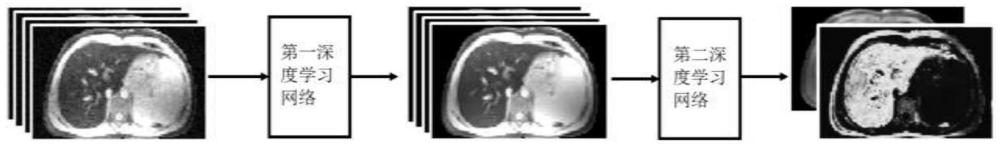

| 摘要: | 本发明公开了一种基于深度学习网络的磁共振R2*参数量化方法,该方法包括:使用第一深度学习网络对输入磁共振T2*加权图像进行去噪声处理;同时使用第二深度学习网络对经过噪声处理后的磁共振T2*加权图像进行磁共振R2*量化预测;所述第一深度学习网络和所述第二深度学习网络组建级联网络。使用深度学习算法对R2*参数进行量化,避免了传统算法的复杂性,减小了量化误差,提升了计算速度,缩短了计算所需的时间。 | ||||